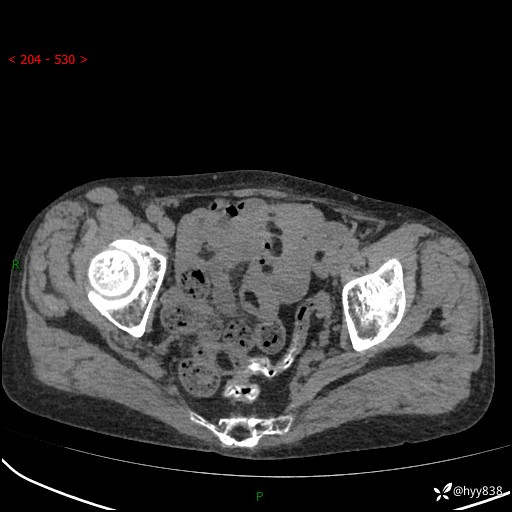

全腹部CT平扫